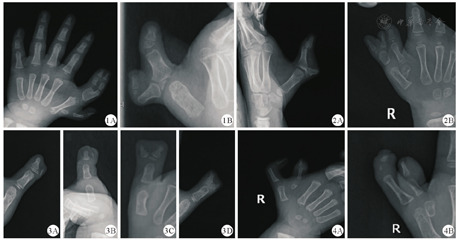

经过临床医师的仔细阅片,本组资料中仍有238指(11.0%)特殊病例无法按现有Wassel分型方法进行分型,荷兰Dijkman等[8]对520例多拇畸形进行分型,全部病例均可使用Rotterdam分型系统进行归类,40%病例无法归入Wassel分型系统。但苏森等[2]统计的结果显示仅有8.6%的多指无法归入Wassel分型系统;本组资料显示11.0%的病例无法归入Wassel分型系统(图1,图2,图3,图4)。对于特殊难以分型病例,高伟阳等[12]以拇指末节指骨形态和轴线偏移为依据进行新的分类并制定对应的治疗方案,术后效果满意。南国新等[13]提出非典型Wassel Ⅵ型并制定相应的治疗方案,治疗效果满意,减少了并发症。随着病例数量的增加,会出现较多特殊、难以归类的病例将重新分型或归类,为指导临床治疗奠定基础。减少手术并发症。

本研究多拇影像学分型采用Wassel分型分类方法,包括Ⅰ型远节指骨分叉型、Ⅱ型远节指骨复指型、Ⅲ型近节指骨分叉型、Ⅳ型近节指骨复指型、Ⅴ型掌骨分叉型、Ⅵ型掌骨复指型和Ⅶ型3节指骨型[9]。其中Ⅳ型发病率最高,占复拇指畸形的43%~46%;Ⅱ型占15%~17%[10]。本回顾性研究能获取影像学资料的多拇畸形总计2 263例(200例未查到影像学资料),其中有238例(283指)无法按Wassel分型方法归类。在各型中,Ⅳ型最多,共905指,占35.3%;Ⅱ型其次,共351指,占13.7%;第三位是Ⅴ型,共243指,占9.5%;第四位是Ⅶ型,共233指,占9.1%;Ⅰ型的例数最少,比例最低,共67指,占2.6%;特殊及无法分类病例,共283指,占11.0%(表3)。数据与国内外其他研究的数据存在差异(表4)。存在283指特殊病例,无法按Wassel分型归类。